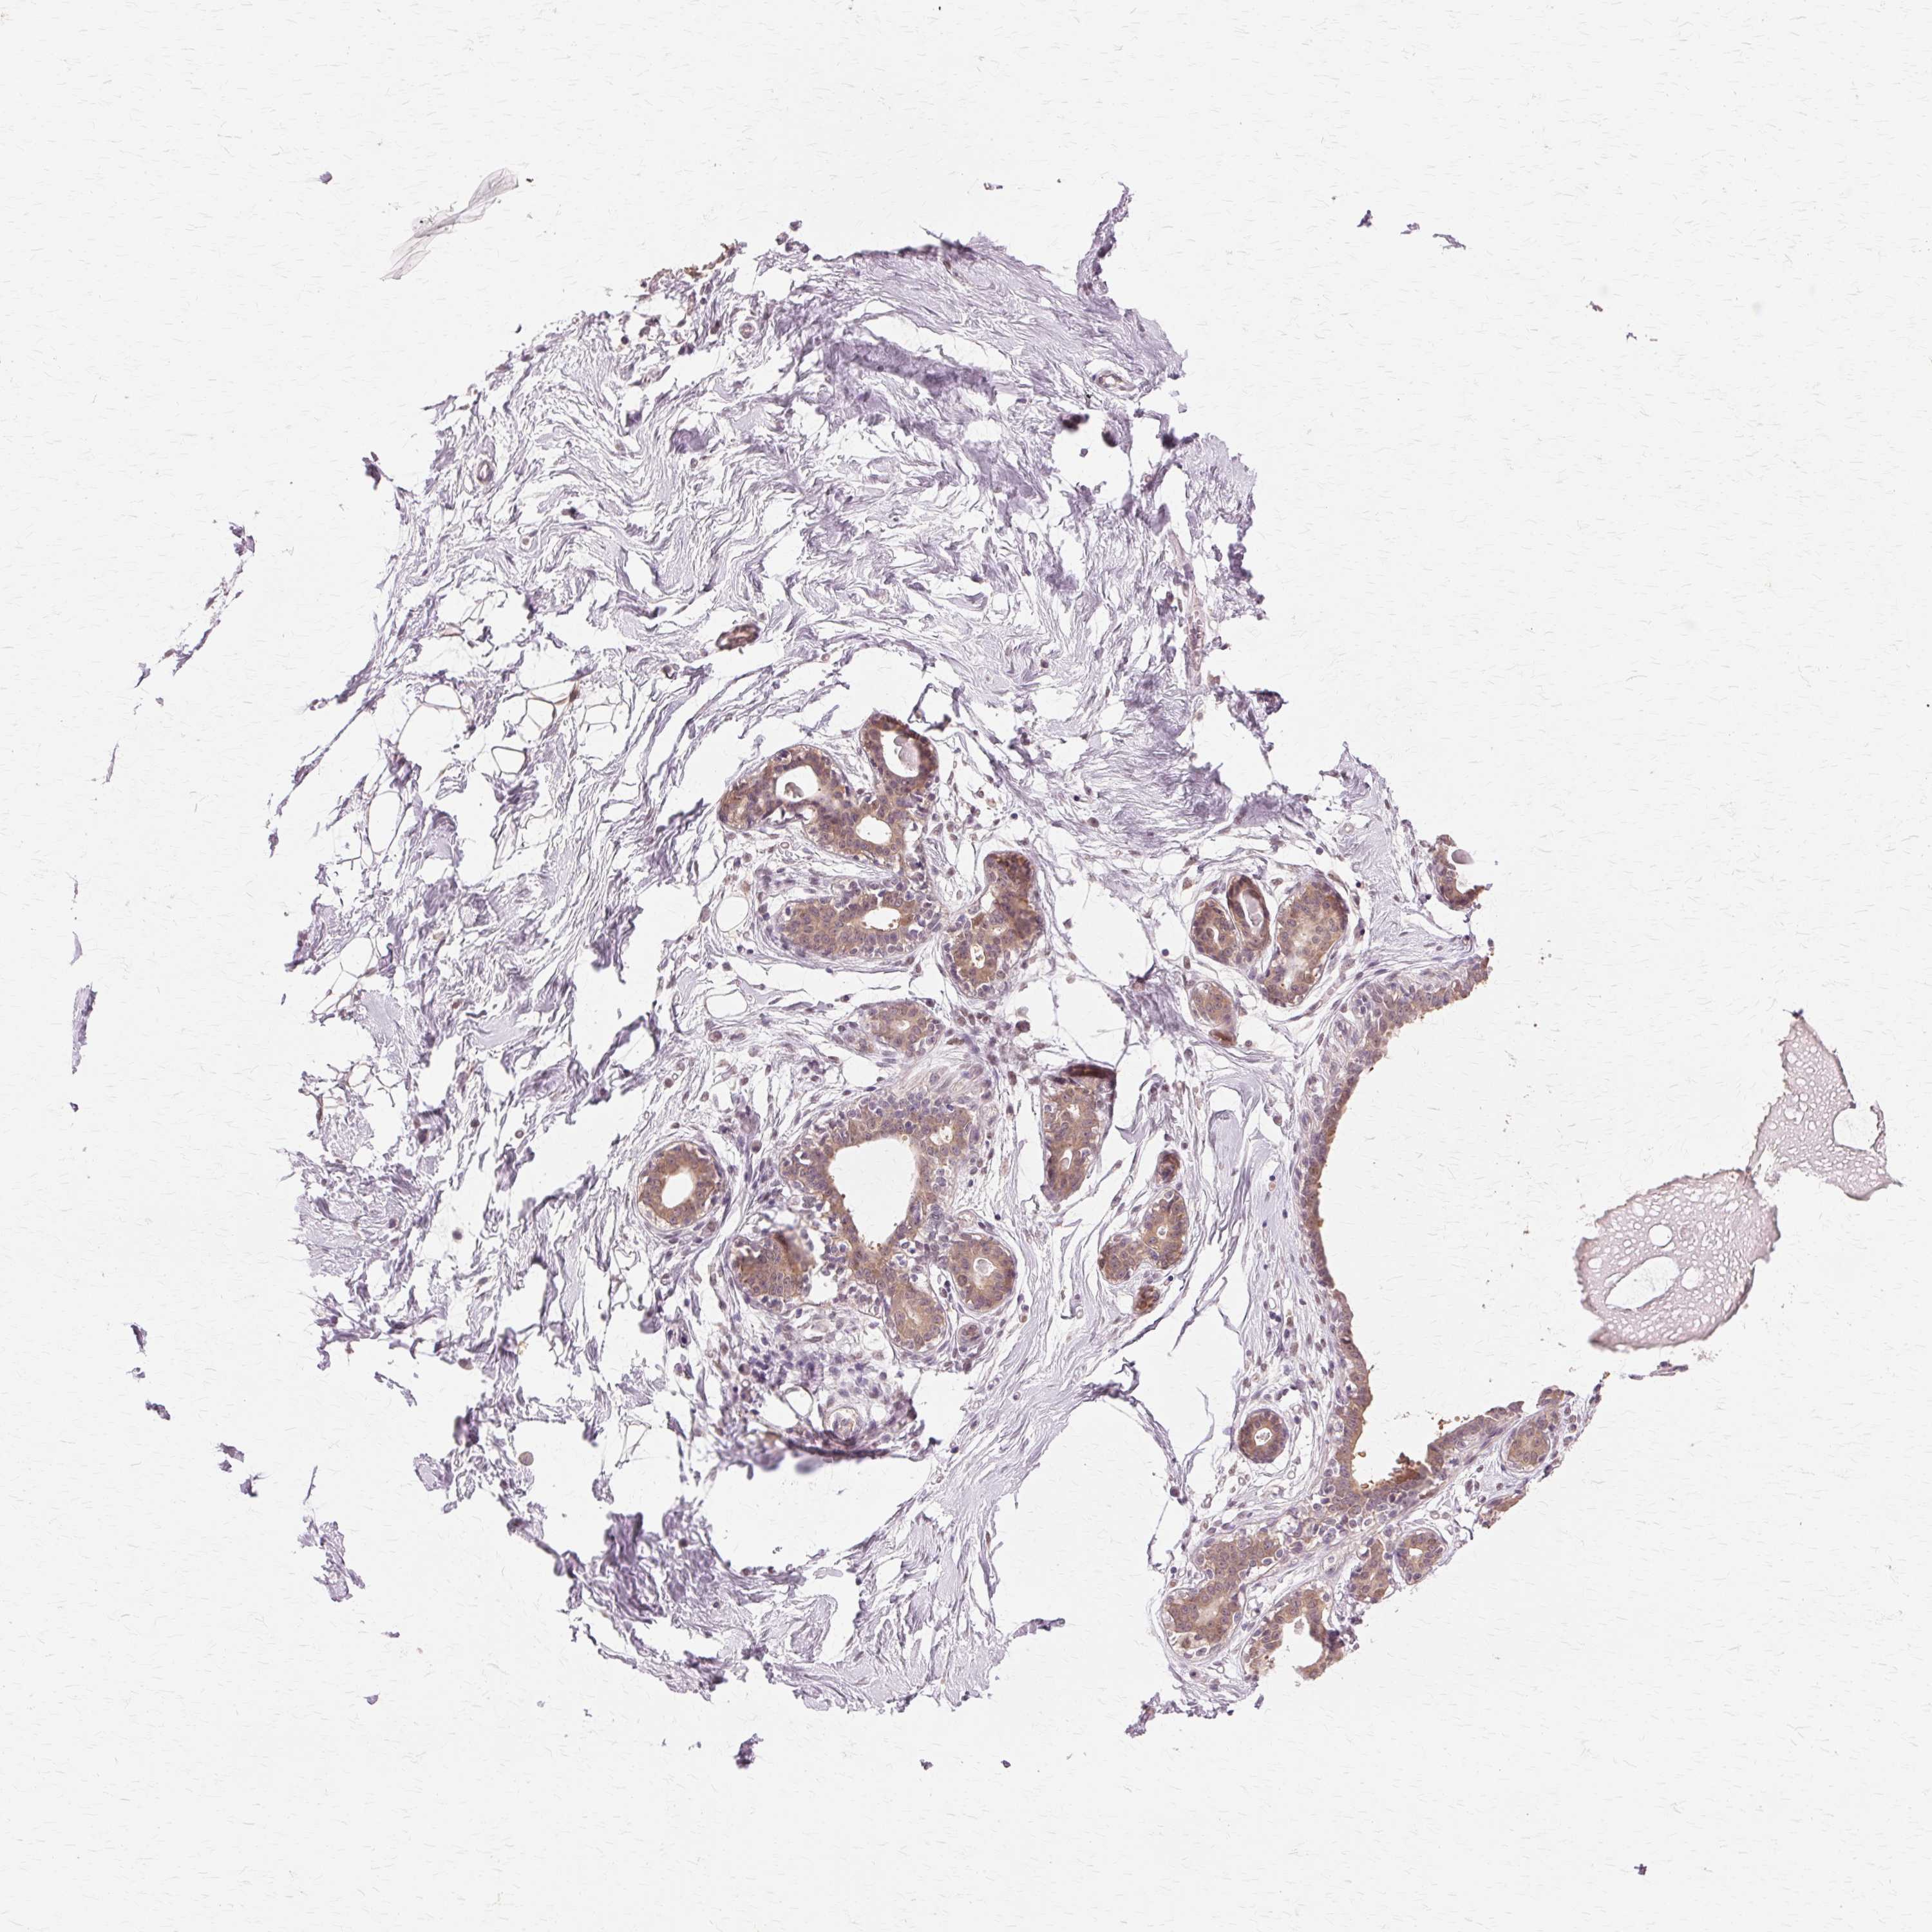

Antibody staining in the annotated cell types in the current human tissue is reported as not detected, low, medium, or high. This score is based on the staining intensity and fraction of stained cells.

Information about each individual sample is listed below, including gender, age, a tissue section image and estimated fractions of cell types. pTPM (transcripts per million) values give a quantification of the gene abundance which is comparable between different genes and samples.

Glandular cells: 5 Adipocytes: 15 Other cell types: 80

Female, age 47

Breast sample 405 pTPM: 51.3

Cell types%